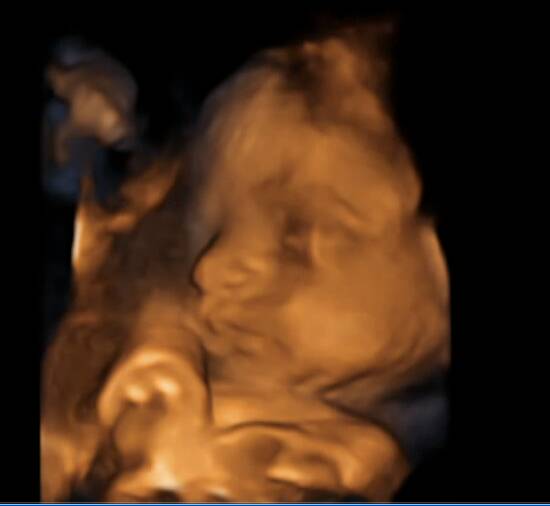

Annte już 19 tydzień

) ii jesteśmy po drugich prenatalnych.. mamy na piśmie że to "prawidłowe żeńskie narządy płciowe" także Michał zostaje sam na placu boju

) a poza tym wszystko ok, tylko Malutka strasznie szybko rośnie - przeciętnie podobno dziecko w tym okresie ma ok 200-250 gram, a nasza już 321

) i długość kości udowej wykracza ponad normę